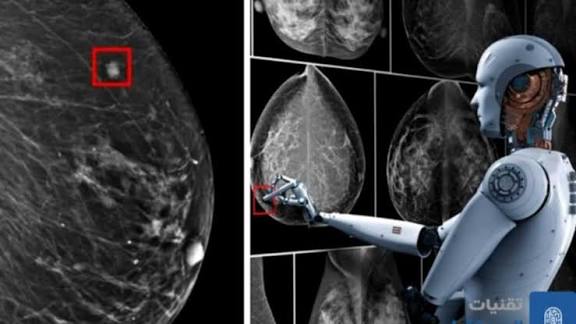

Recherche médicale : l’IA au service du diagnostic précoce du cancer du sein en Algérie

L’Intelligence artificielle (IA) s’impose comme un outil essentiel d’accompagnement du secteur de la santé, incitant les chercheurs algériens, porteurs de projets innovants, à développer des solutions avancées pour le dépistage précoce du cancer du sein, l’une des formes les plus répandues de cette pathologie dans le monde.

Parmi ces initiatives remarquables, figure celle menée par une équipe dirigée par la chercheuse au Centre de développement des technologies avancées (CDTA), Fatiha Alim Ferhat, à l’origine d’un programme intelligent, en mesure de détecter les variations microscopiques des tissus, révélant l’existence d’une tumeur.

Le programme s’appuie sur une base de données médicales « riche et continuellement alimentée », lui permettant de reconnaître les différents types du cancer et d’assurer, ainsi, un dépistage fiable avec un haut degré de précision. « Cet outil permet un diagnostic rapide, facilitant la prise de décisions médicales, ce qui contribue, par conséquent, à renforcer l’efficacité des consultations périodiques et à encourager le dépistage précoce, augmentant, ainsi, les chances de guérison », a-t-elle déclaré à l’APS. Le second projet prometteur est celui de Ahmed Ilyes Bensalem, étudiant à l’Ecole supérieure d’Informatique de Sid-Bel-Abbès, dont la spécialisation en IA a permis la conception d’un programme médical dédié au dépistage du cancer, qui repose sur l’analyse rapide des échantillons issus des biopsies.